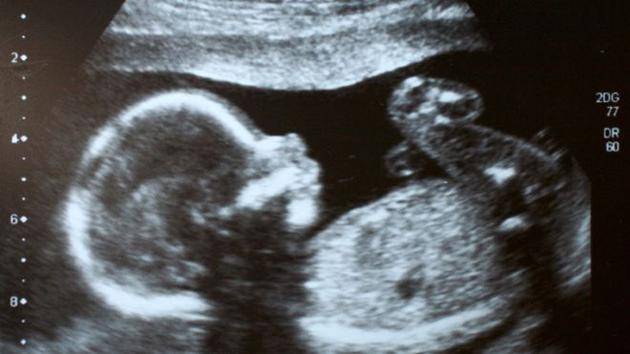

编辑基因以改变后代的质量或创造超人至少有几个环节,一是部分基因编辑,二是胚胎基因编辑,三是把经过基因编辑的胚胎植入人体以诞生基因改造后的后代(包括矫正了疾病基因的正常人和超人)。现在,研究人员在胚胎基因编辑方面有了一些成果,但离用基因编辑后的胚胎孕育人,无论是创造超人还是根治了疾病的普通人还有很大的距离。

2015年4月,中山大学生命科学学院的黄军就副教授等人利用基因编辑技术CRISPR/Cas9(基因剪刀)对人胚胎中会导致地中海贫血的β珠蛋白基因突变成功地进行编辑修饰,希望利用这一方式来根治地中海贫血。尽管试验的胚胎在试验后被遗弃了,但还是引发了全球对编辑胚胎基因的担忧。

2017年9月20日英国伦敦弗朗西斯•克里克研究所的尼亚肯团队在《自然》杂志发表了编辑人类胚胎基因的成果。利用CRISPR/Cas9对胚胎DNA进行精准剪切,关闭了一种名为OCT4的基因,该基因在胚胎发育早期非常重要。